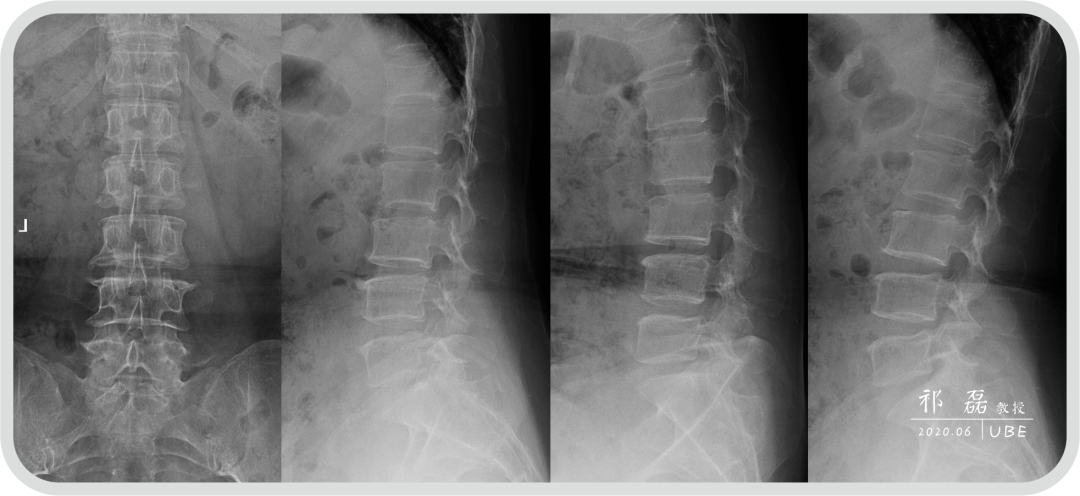

患者:吴某,女,53岁,腰痛及双下肢疼痛麻木5年余,加重1月余,间歇性跛行约200米。于近日入我院查体,下腰椎棘突及椎旁肌深压痛,双下肢感觉运动正常。双侧直腿抬高试验(-),双侧踝反射(-),入院诊断为:腰椎管狭窄症。

图1:腰椎正侧位+过伸过屈位X线